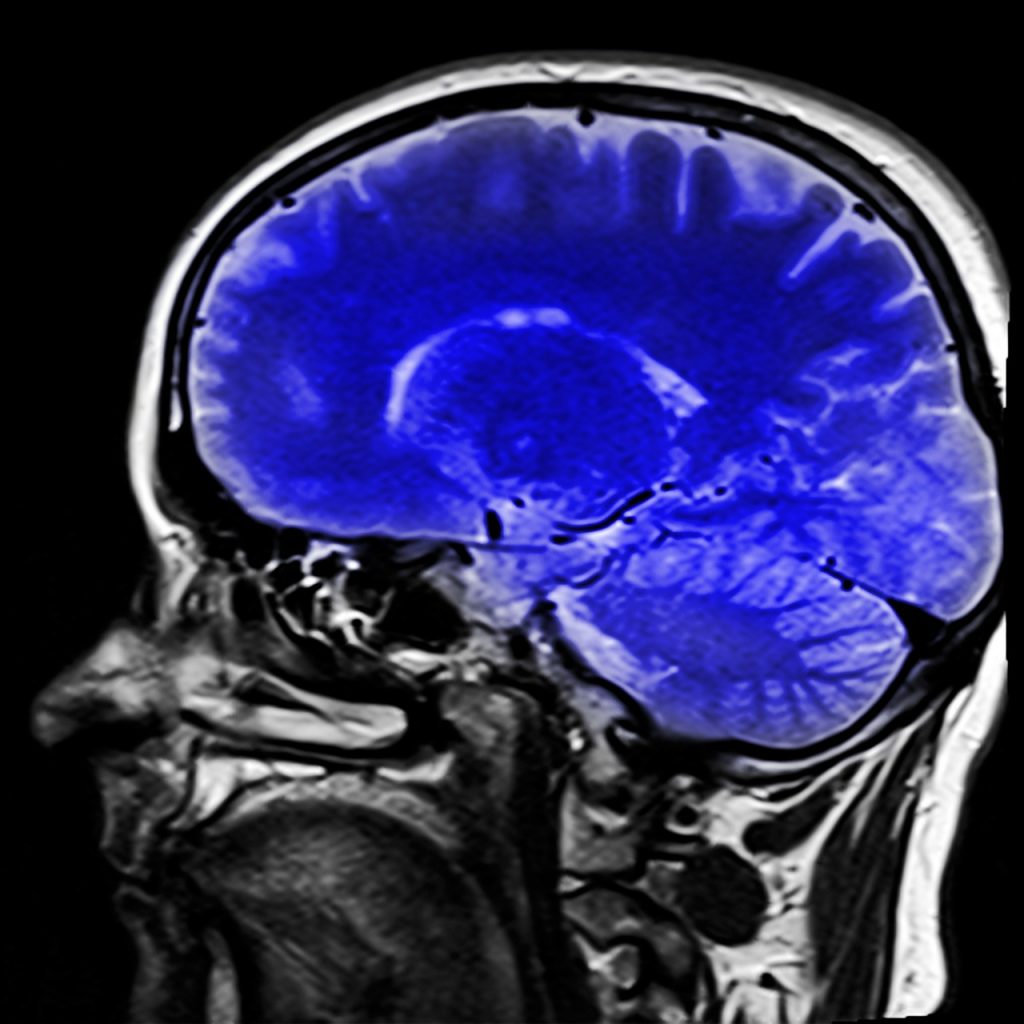

Last week we spoke about the physical withdrawal symptoms from drugs and alcohol (which can be read here). Drugs and alcohol also have a severe effect on the neurochemistry of the brain, which is what we will be discussing today. In order to understand these effects, we need to know how the brain responds to both endogenous and exogenous chemicals. Endogenous chemicals are naturally produced by the body and are known as neurotransmitters. Exogenous chemicals are not naturally produced; they are introduced to the body when one uses drugs or alcohol. In order for us to understand the long term effects regarding neurochemistry; first we need to understand neurotransmitters.

Neurotransmitters: Transmit signals across a chemical synapse from one neuron to another. They play a major role in shaping everyday life and functions. Listed below are the select neurotransmitters we will be discussing today and how they are affected by Alcohol, Opiates, and Cocaine.